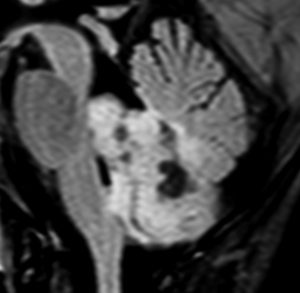

小脳毛様細胞性星細胞腫のFLAIR画像所見

壁在結節を伴うのう胞性小脳毛様細胞性星細胞腫は,結節を手術摘出すれば治癒するものです。しかし,あたかも腫瘍が残っているようなMRI画像所見が残ることがあります。

この例は,10歳の子どもに無症状で偶然発見された大きなのう胞性小脳毛様細胞性星細胞腫です。開頭手術で腫瘍結節は全摘出して腫瘍のう胞は縮小したままです。(画像はクリックすると拡大して見えます)

開頭手術で白く増強される結節部分だけを摘出しました。MIB-1はやや高値で3%と報告されました。病理組織診断は,WHO grade 1 毛様細胞性星細胞腫です。

6年後のMRI FLAIR画像です。摘出腔周囲の高信号域が残存しています。ここまで残ると腫瘍周辺浮腫ではありませんし,腫瘍細胞が左小脳半球に広範囲に浸潤して残存しているものだと判断されます。しかし,6年間で病変の増大傾向がありませんでした。この残存腫瘍(らしい所見)に対して放射線治療や化学療法を行うべきかどうか,結論は出ていません。しかし,経過観察を続けても増大して来ない例があることは確かです。一方で,この高信号領域が拡大したり,ガドリニウム増強される病変が再出現して治療がまた必用となることもあります。